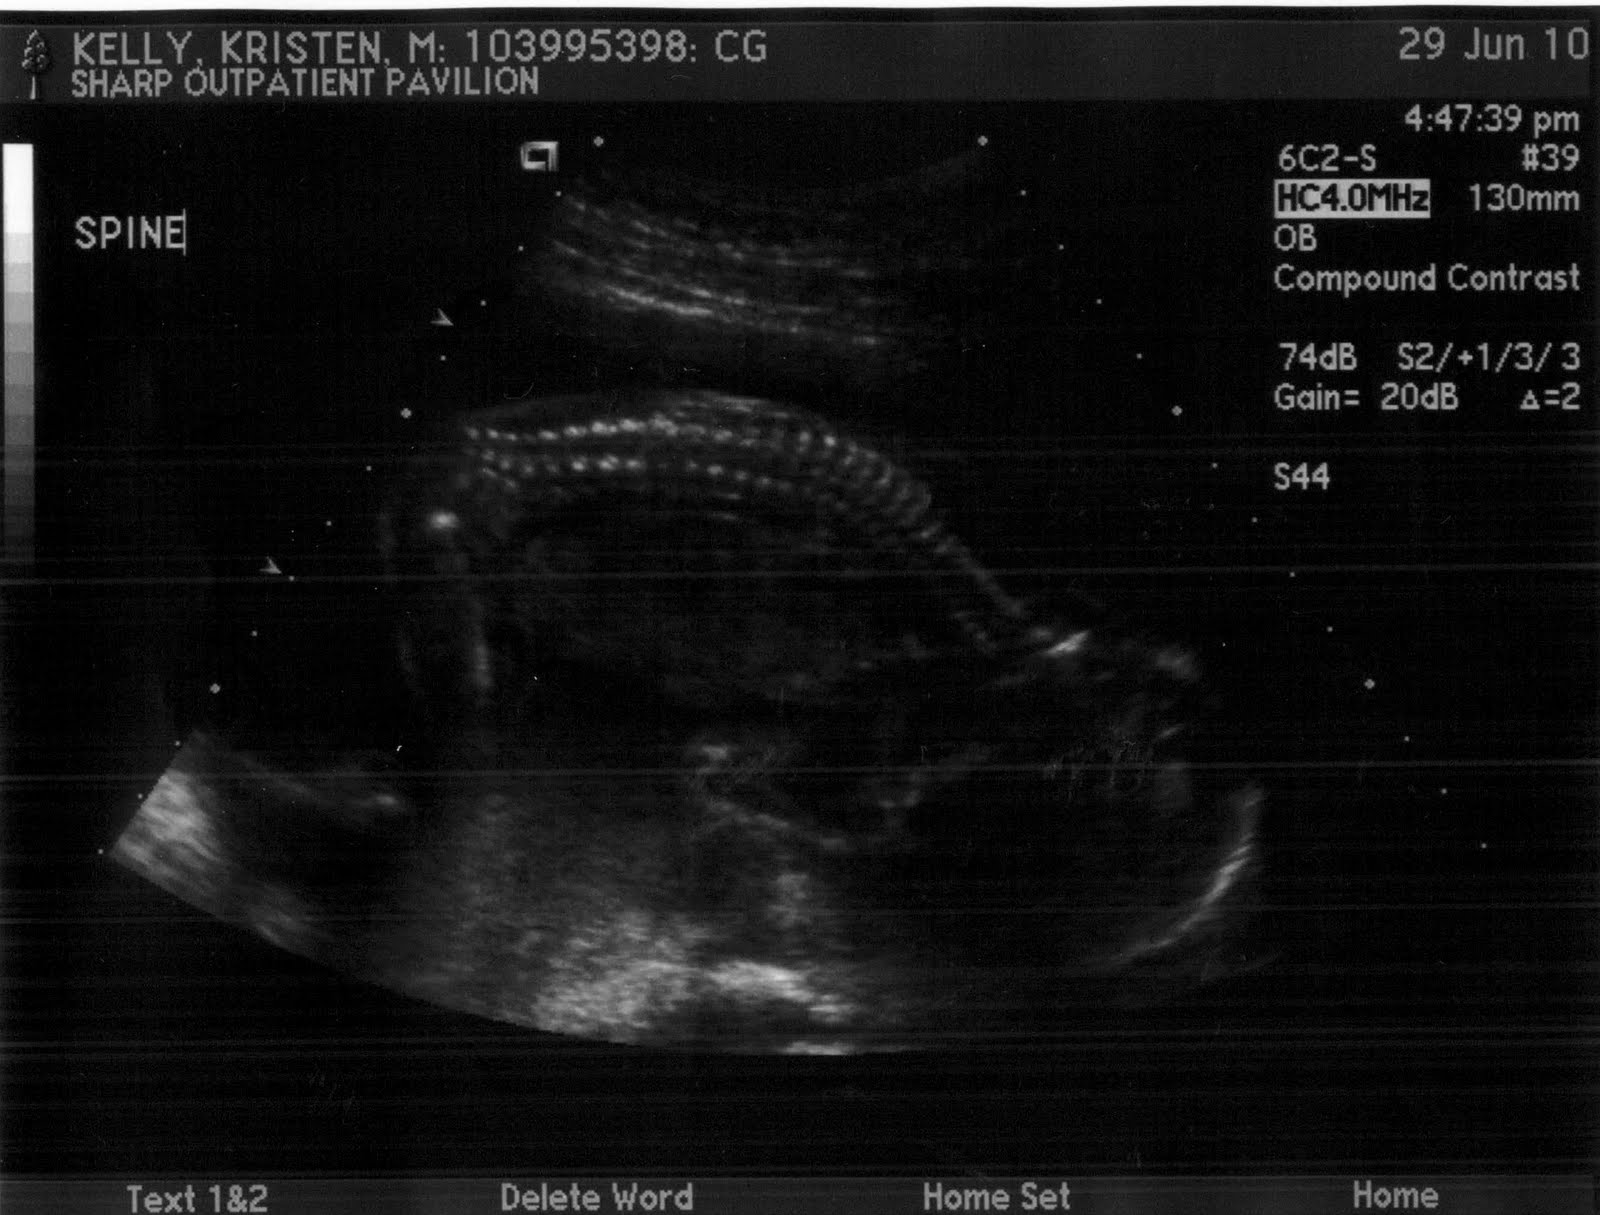

Here are a few shots from the ultrasound showing her little face, spine, and crossed legs - she's a modest lil one!